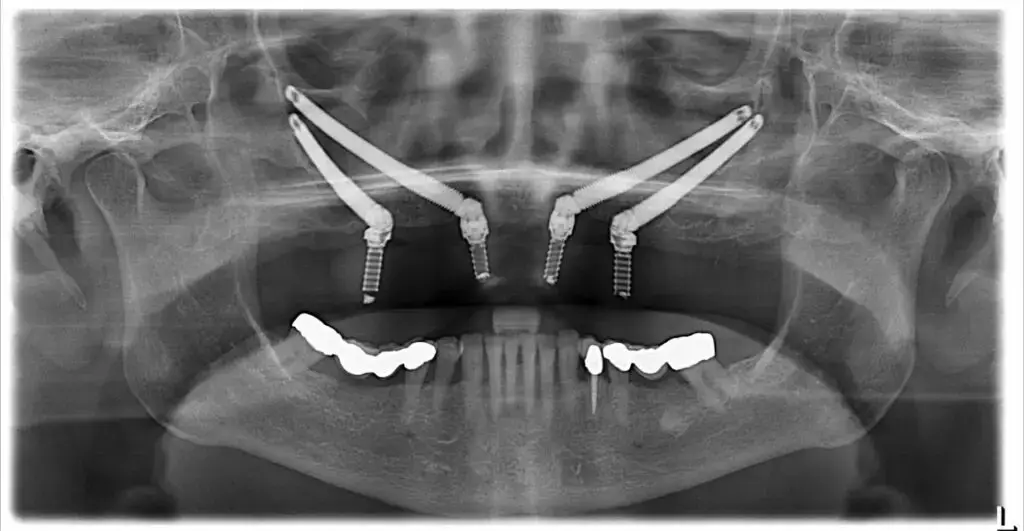

Имплантация All-on-4 — это революционное решение для людей, потерявших большинство или все свои зубы.

Имплантация All-on-6 — это еще один превосходный вариант для тех, кто потерял большинство или все свои зубы.

Получите имплантаты без костной пластики! Зигоматические имплантаты в Турции — это передовое решение для пациентов с недостатком костной ткани в верхней челюсти. Эта методика позволяет немедленно установить протез, минуя необходимость длительной костной аугментации. Узнайте больше в клиниках Cayra.

Вам необходим синус-лифтинг для установки имплантатов в Турции? Клиники Cayra предлагают безопасную и эффективную аугментацию синуса. Мы проводим синус-лифтинг с костной пластикой, чтобы увеличить объем костной ткани. Это обеспечивает стабильность и долговечность ваших дентальных имплантатов.